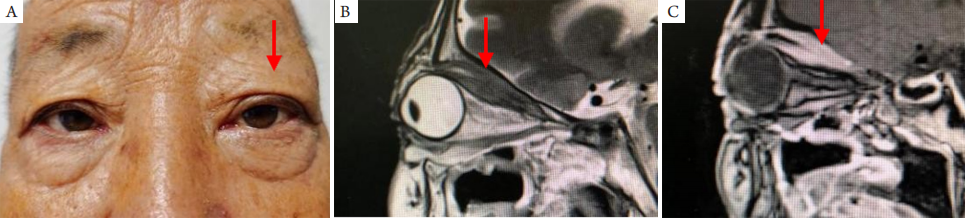

2.5 原发眼肌型

原发于眼外肌的MALT淋巴瘤少见[22],早期即可出现复视和上睑下垂,继之出现眼球突出或移位,检查可见眼睑轻度肿胀、受累肌止点处结膜充血肥厚、眼球和眼睑运动受限。影像学检查受累眼外肌多为全长弥漫肥厚。眼肌型MALT淋巴瘤可见于各条眼外肌,但以上直肌和提上睑肌受累多见(图5)。

眼眶型MALT淋巴瘤可累及单条或多条眼外肌,应与原发眼肌型病变区别[22-23]

20230619102916_6307.png

图5 原发性眼外肌型MALT淋巴瘤

Figure 5 Primary MALT lymphoma of the extraocular muscle

(A)外观像:显示左眼睑稍肿胀;(B)T2WI 矢状位图片:显示上直肌和提上睑肌全长肥厚,中等偏低信号;(C)压脂强化矢状位片:显示病变区明显强化。箭头示病变部位。

(A) Slight swelling of the upper left eyelid; (B) Sagittal T2WI image showing full-length hypertrophy of the superior rectus and the elevator palpebrae superioris with hypointensity; (C) Sagittal image with fat suppression and enhancement showing significant enhancement in the lesion area. Arrows indicate the lession.